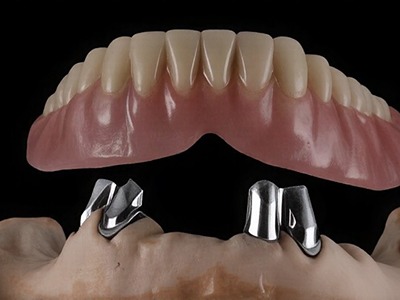

You can rely on us for dependable, comfortable, and expert dental care. With advanced technology, experienced specialists, and personalized treatment plans, we ensure every patient receives trusted, effective solutions for long-term oral health and confident smiles.

Dr Nitesh Rai, specializes in replacement of teeth with complete dentures, removable partial dentures, fixed partial dentures and Implants.